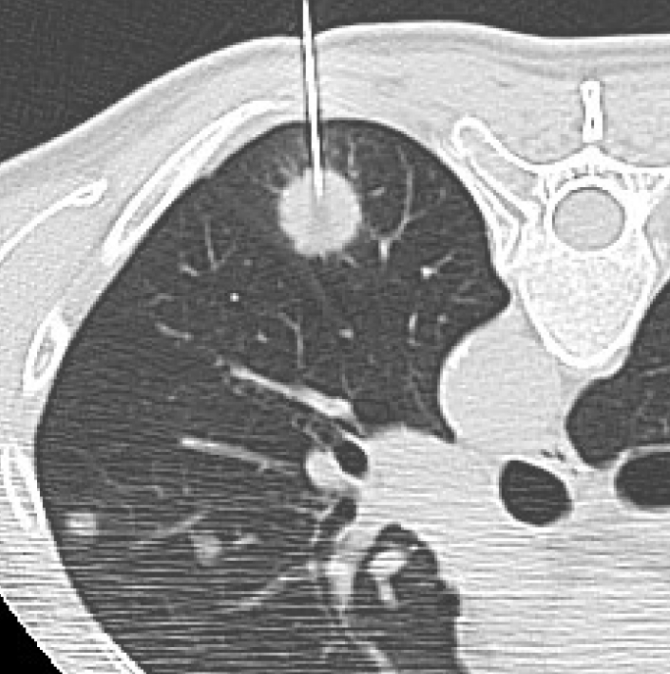

Q5. 흉부CT에서 종양이 발견되면 바로 조직검사를 하나요?

A. 꼭 그렇지는 않습니다. 결절이나 종양이 발견되더라도 크기, 모양, 경계, 주변 혈관과의 거리 등을 종합적으로 판단한 후 결정합니다. 크기가 작고 둥글며 경계가 뚜렷한 경우는 양성일 가능성이 높아 3~6개월 후 추적검사를 하기도 합니다. 그러나 비정상적인 모양이나 크기 변화가 빠른 경우에는 조직검사(생검)를 진행합니다.